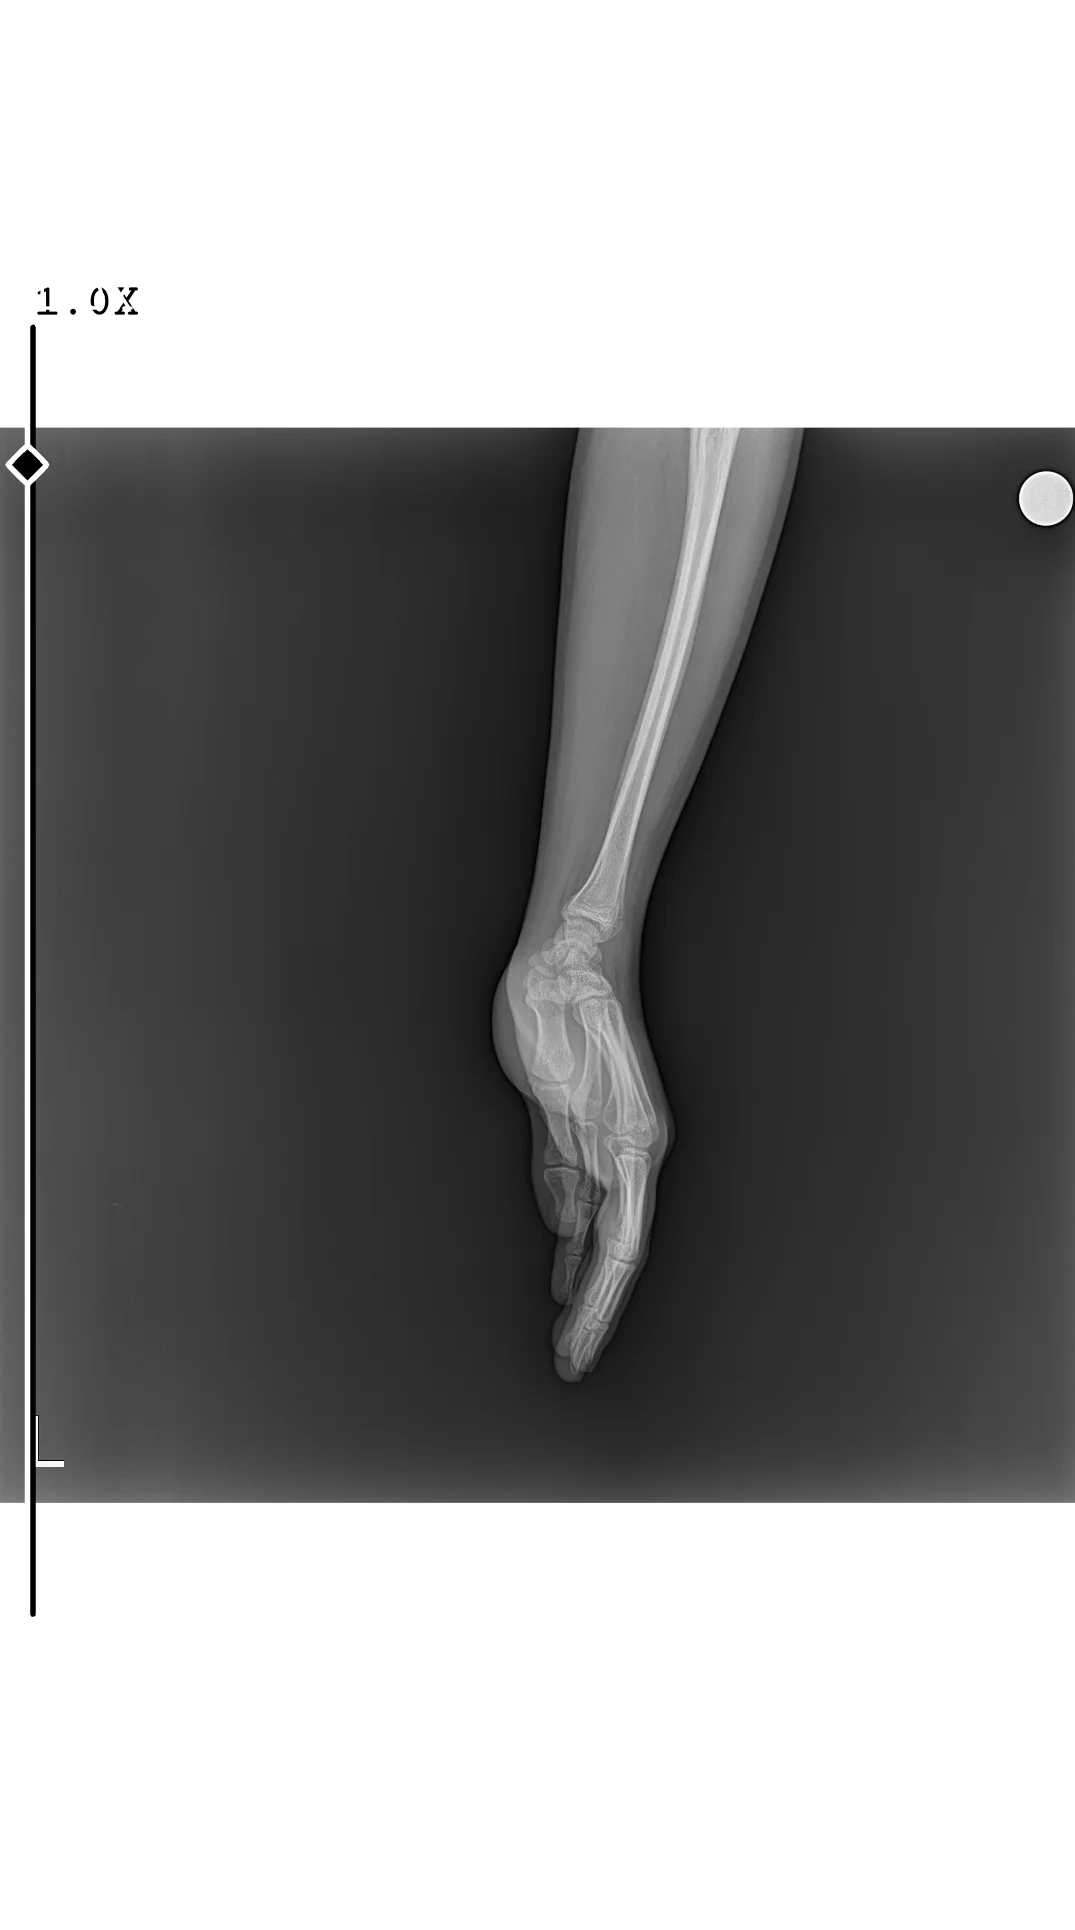

Doktor bir şey demedi mi ve bende çektirmek istiyorum hangi bölümden randevu aldın

endokrinoloji bölümünden alabilirsin ama ben gitmedim halihazırda çekinilmiş röntgenim vardı zaten WhatsApp aracılığıyla gösterdimDoktor bir şey demedi mi ve bende çektirmek istiyorum hangi bölümden randevu aldın